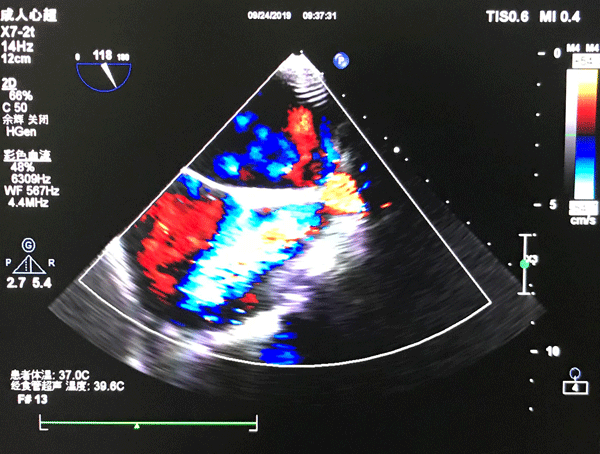

彩色多普勒显像

9月24日一早,患者在家属及主管医师陪同下一同来到超声科6室,诊室内麻醉师李超峰,护士张妮已经准备好麻醉药品,心电监护仪等设备,麻醉师李超峰在和患者认真沟通后,确认患者可以实施无痛经食道超声心动图检查。检查过程中超声科主任李培英、主治医师吕品认真观测彩超机上心动图显示,护士张妮和麻醉师李超峰则密切关注患者情况,检查顺利,患者情况稳定,经过短暂休整,患者由主管医师及家属陪同安返病房。检查结束后,科主任李培英及主治医师吕品经过对超声图像的分析为患者出具了准确的诊断报告。